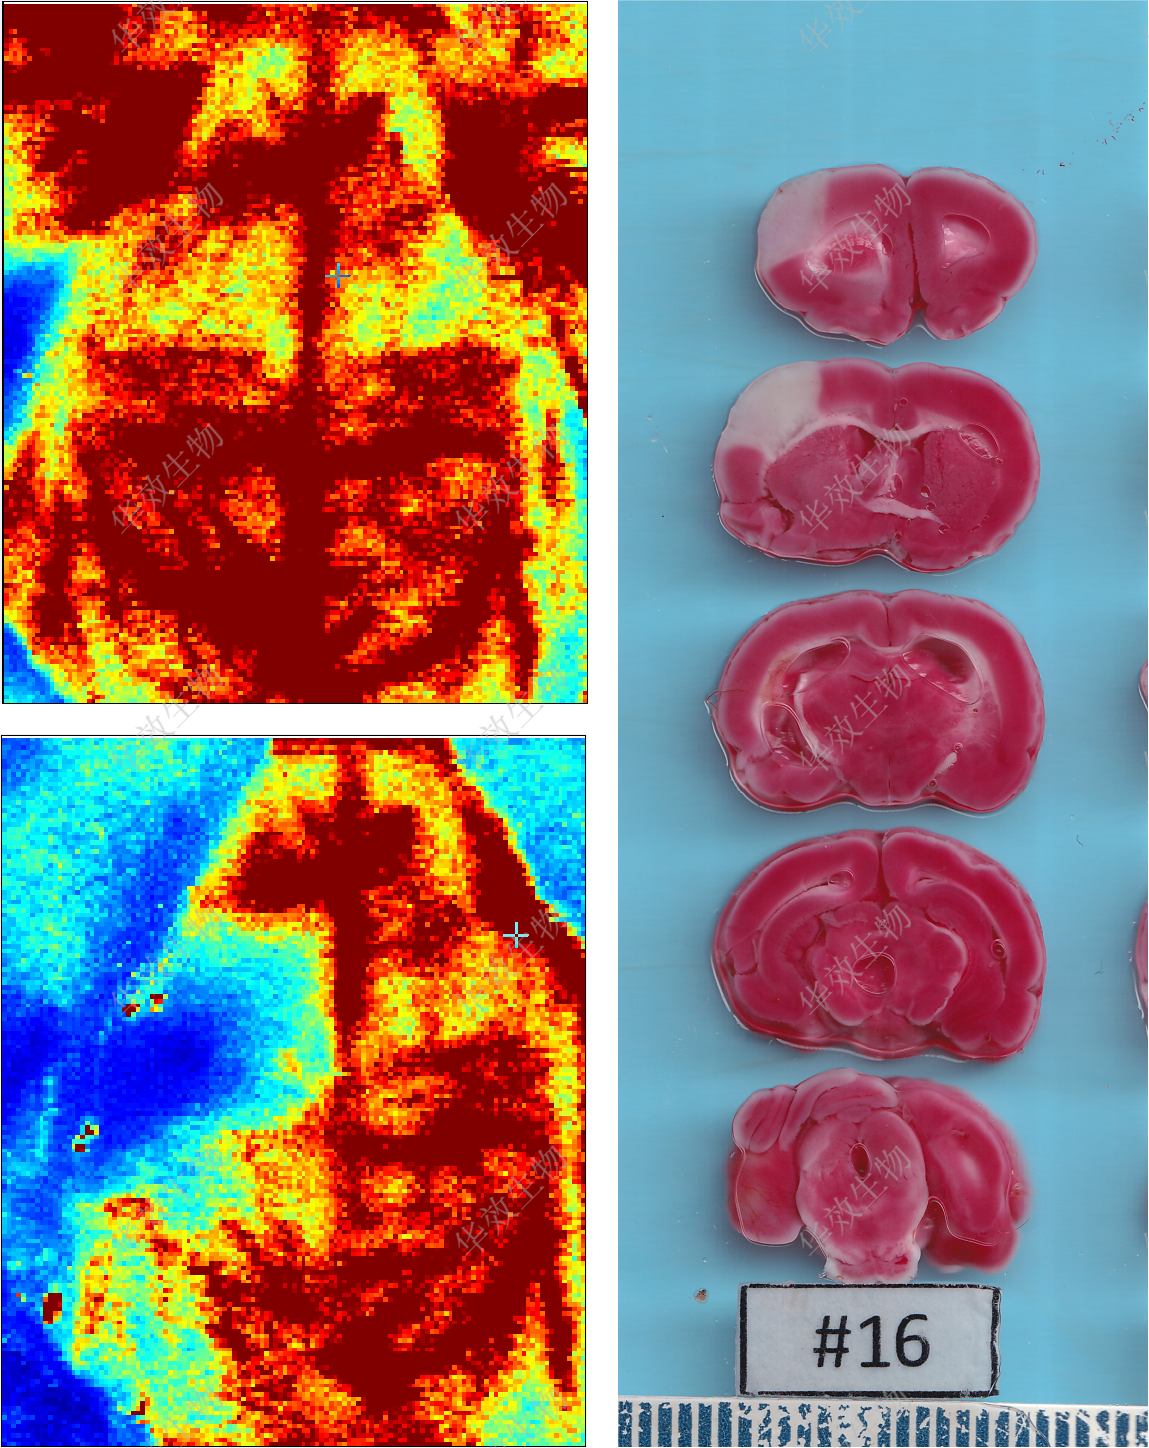

脑卒中

缺血再灌注性脑卒中模型MC…

光化学诱导的缺血性脑卒中…

胶原酶诱导的出血性脑卒中…

永久缺血性脑卒中模型